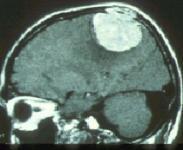

• 腦膜瘤

腦膜瘤分為顱內腦膜瘤和異位腦膜瘤,前者由顱內蛛網膜細胞形成,后者指無腦膜覆蓋的組織器官發生的腦膜瘤,主要由胚胎期殘留的蛛網膜組織演變而成。好發部位有頭皮、顱骨、...